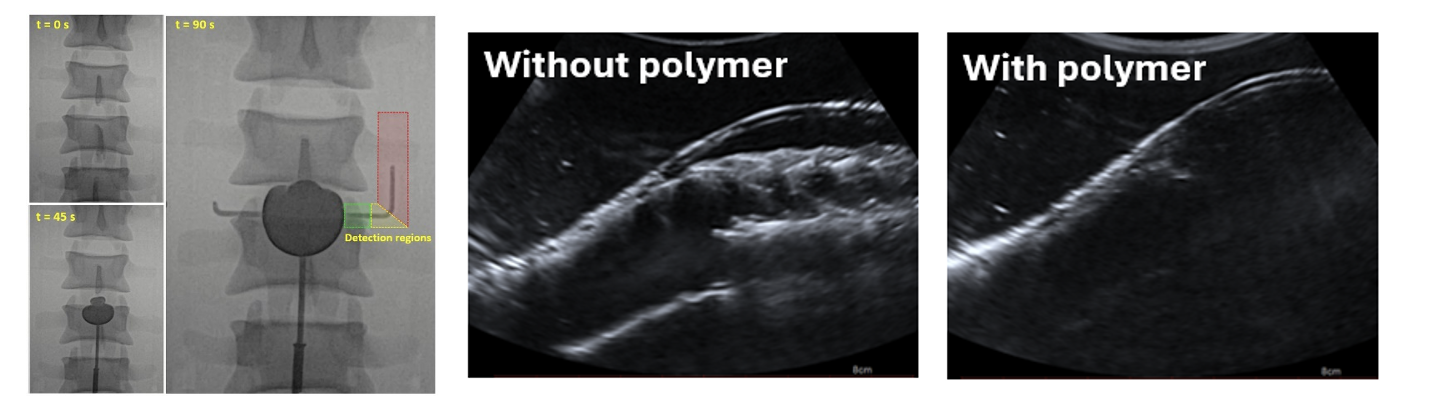

Several aspects were investigated through the use of clinically relevant, physical models of the abdominal aorta, which were designed and developed in-house (Figure 1). These models were used to investigate imaging techniques, both during injection of the polymer and during follow-up after the treatment (Figure 2). It was found that the contrast in the polymer can be reduced by ~33%, reducing artifacts on computed tomography (CT) typically used for follow-up, while retaining sufficient detectability for safe injection. It was also found that ultrasound, another commonly used follow-up technique, is not suitable after polymer injection because the polymer significantly weakens the measured ultrasound signals. Finally the effect of the polymer on the natural motion of the aorta and stent graft was investigated. These insights help bring the polymer technique closer to clinical practice.

Figure 2. Imaging results of models with polymer injections; X-ray measurements during injection, at several timepoints (left) and ultrasound measurements during follow-up, without polymer, showing the vessel wall and stent graft (middle), and ultrasound measurements with polymer, only showing the top vessel wall and obscuring the stent graft and bottom wall